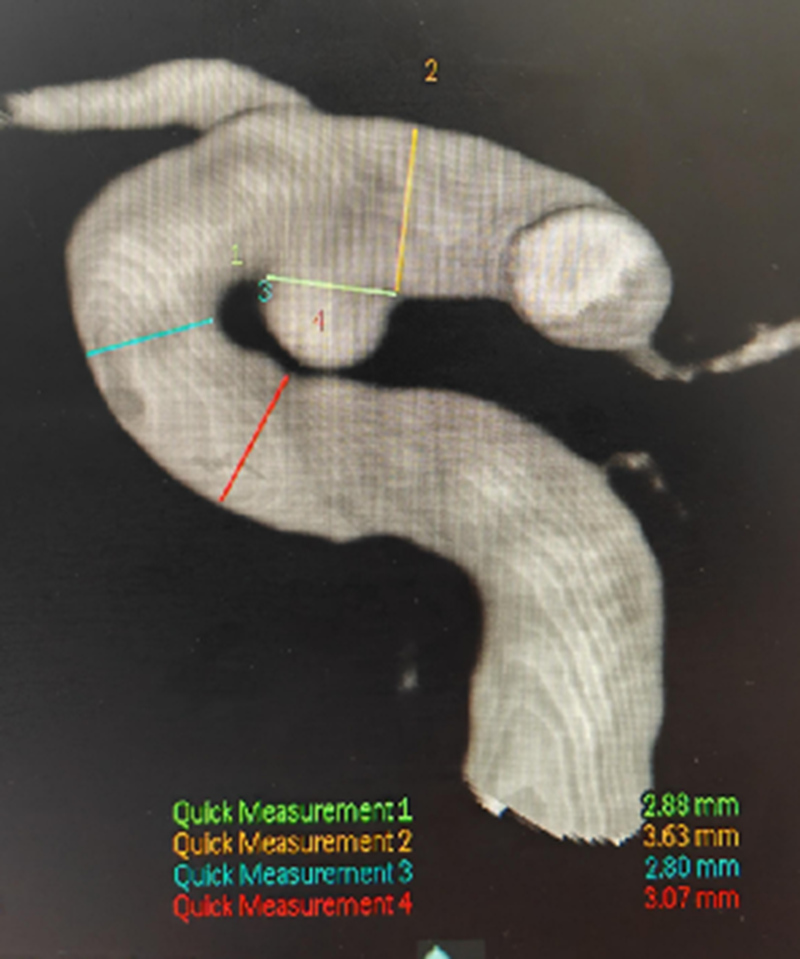

密网支架覆盖长度

▲术前3D测量

经检查,张某左侧颈内动脉C6段可见异常隆起,大小约为:2.6mm×2.1mm×2.3mm,考虑为动脉瘤,神经外科医疗团队经过多学科会诊和论证,决定为其实施目前国内外先进的血流导向装置进行介入治疗。